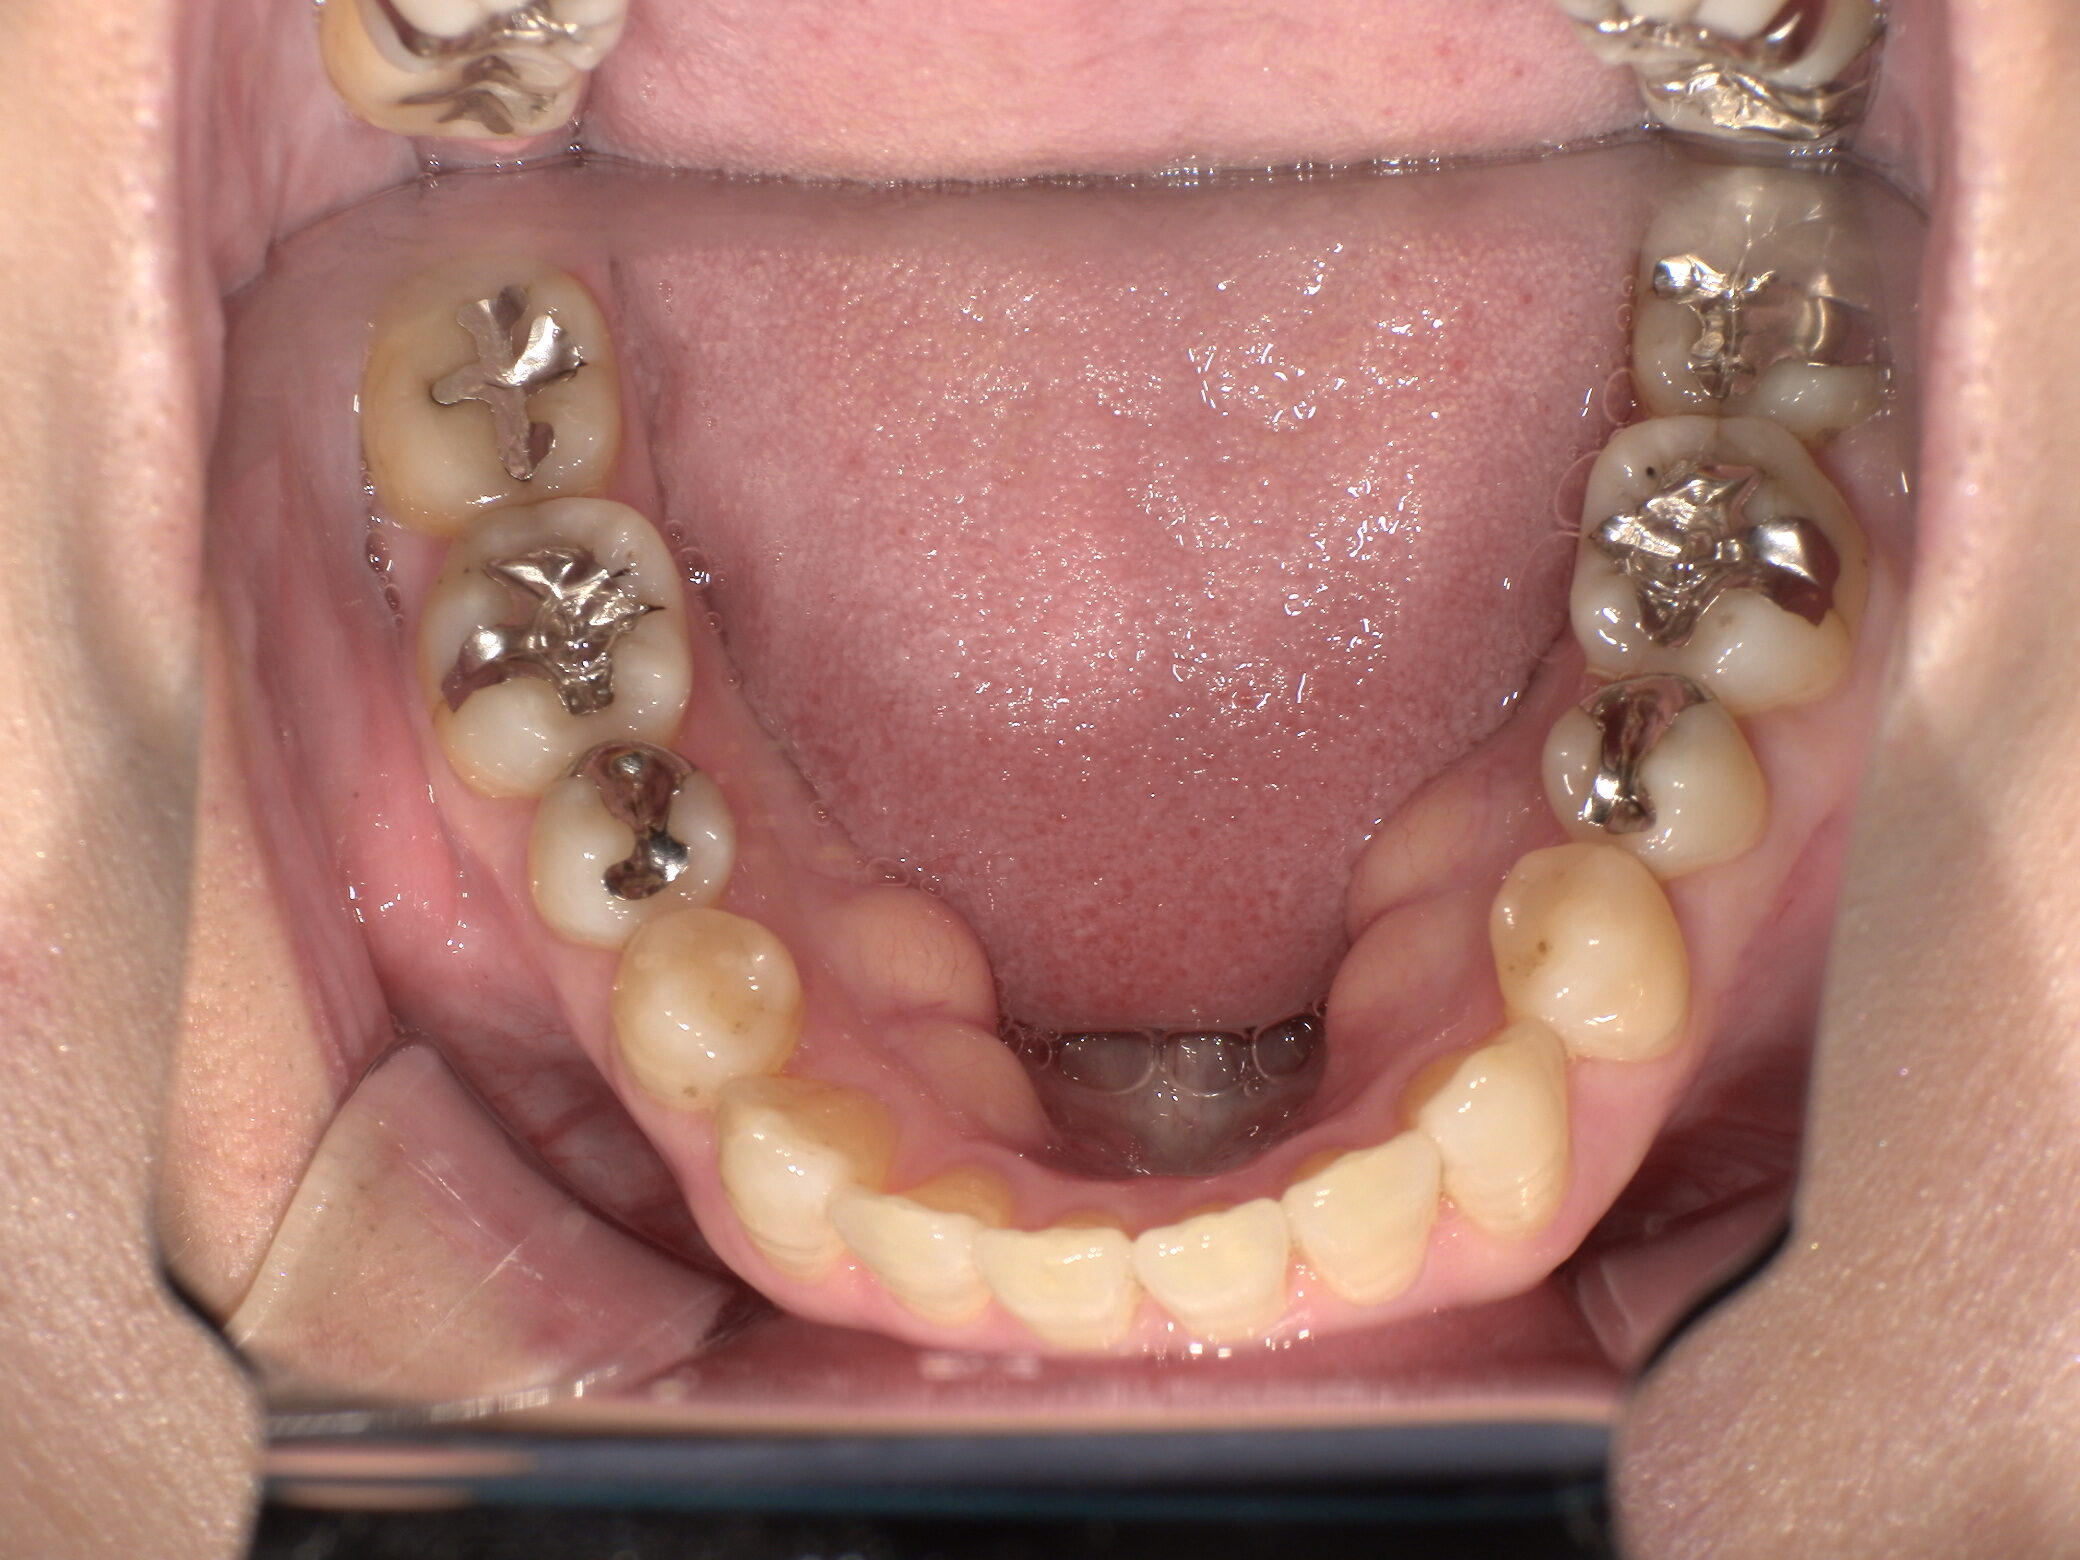

治療前 ![]() |

銀歯の見た目が気になること、詰め物の下のむし歯が心配とのことで来院されました。 |

| カウンセリング・診断結果 |

既存のメタルインレー周囲に変色および適合不良が認められ、二次カリエスを確認しました。審美的な問題だけでなく、今後のむし歯再発リスクも考慮し、再治療が必要と判断しました。 |